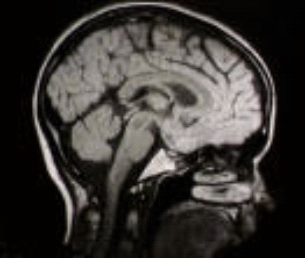

A CAT scan of the inside of a head.

Essentially these imaging methods take two forms. X-ray and ultrasound methods use a source of radiation that lies outside the body. The radiation is detected after it has passed through the body, and an image constructed from the way it has been absorbed. When X-rays are used, this process is called computerised axial tomography or CAT for short. (The word tomography comes from the Greek work tomos meaning "cut" or "slice".) This article will look at this process in detail.

I really liked the article. I'm trying to learn more about the fundamentals of this kind of equipment after medical school. The image at the beginning is a sagittal T1 weighted MRI (rather than a CT that is gathered axially). You can tell because the fat is high signal and bone is low whereas CT would have bright bone and less contrast within the brain.

Hounsfield also won the Noble Prize. And although he used McCormack's work I don't think they collaborated on the scanner. The head photo is a CT Scan, a sagital view of axial images reformatted on the computer. You could not get your head sideways in the scanner